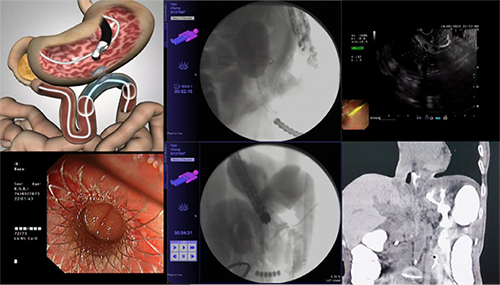

患者在院外诊断为晚期胰腺癌,近期出现恶心呕吐、腹胀反酸等症状,并逐渐加重。入院后内镜检查发现患者病变累及十二指肠球腔,镜身无法通过。考虑到患者已经处于肿瘤晚期、高龄女性(83岁)、全身状况差,尤其合并心肺功能不全,外科手术风险大,且普通的肠道支架效果不理想。综合评估多方面因素,充分与患者家属沟通后,经全科讨论,胡锦华主任医师决定为患者施行EUS-GE以解除患者梗阻症状。经过术前精心准备,24日下午患者被接到内镜中心,在X线引导下,胡锦华主任医师将双球囊送入空肠固定在屈氏韧带附近肠管,在超声内镜穿刺小肠成功后,经内镜、X线双引导顺利完成HOT AXIOS支架置入,从而实现胃空肠吻合。随后X线透视下反复造影,证实连接胃腔与肠腔的支架通畅、无渗漏,手术取得圆满成功。患者术后第2天恢复进食,观察72小时患者病情平稳,胃流出道梗阻的问题得以解决,进食顺畅,大大改善了患者的生活质量,也为后续进一步肿瘤治疗奠定了良好的基础。

超声内镜引导下胃空肠旁路术作为介入性超声的一项高端创新技术,在治疗良恶性胃流出道梗阻(GOO)、输入袢综合征等方面展现出了良好的安全性和有效性。本项技术具有能够快速恢复饮食、术后再狭窄率低、安全性好、超级微创等优点,可作为传统外科胃空肠吻合术的一种替代选择。尤其在HOT AXIOS新技术平台上,操作更为简洁、安全性更高,有希望成为恶性胃出口梗阻姑息治疗的临床优先选择。这是该团队继2017年3月初在国内率先开展双气囊辅助超声内镜引导下胃空肠旁路术(EUS-GE)后持续改进,再次在新技术平台上完成的新技术。